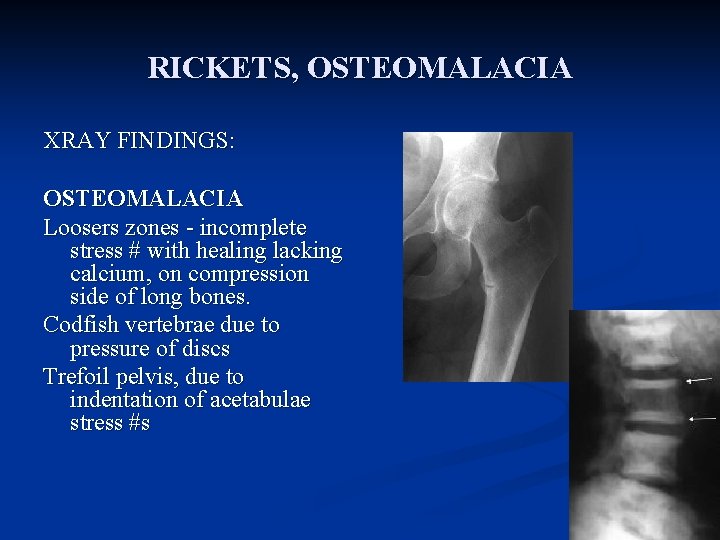

RICKETS, OSTEOMALACIA XRAY FINDINGS: OSTEOMALACIA Loosers zones - incomplete stress # with healing lacking calcium, on compression side of long bones. Codfish vertebrae due to pressure of discs Trefoil pelvis, due to indentation of acetabulae stress #s

Osteomalacia Skeletal pain, proximal muscle weakness n X-ray – Looser’s zones n Laboratory – low PO 4 -, (vitamin D deficiency: low Ca 2+, increased alkaline phosphatase) n n Treat underlying deficiency

Osteomalacia Skeletal pain, proximal muscle weakness n X-ray – Looser’s zones n Laboratory – low PO 4 -, (vitamin D deficiency: low Ca 2+, increased alkaline phosphatase) n n Treat underlying deficiency

Radiological findings of rickets n n n Generalized osteopenia Widening of the unmineralised epiphyseal growth plates Fraying of metaphysis of long bones Bowing of legs Pseudo-fractures (also called loozer zone) n n n Transverse radio lucent band, usually perpendicular to bone surface Complete fractures Features of long standing secondary hyperparathyroidism (Osteitis fibrosa cystica) n n Sub-periosteal resorption of phalanges Presence of bony cyst (brown Tumor)